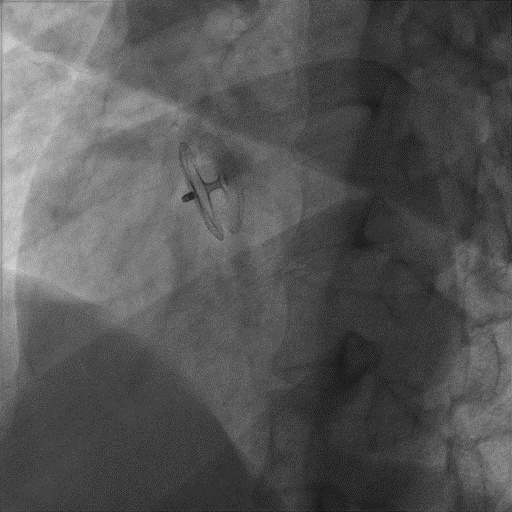

選擇D-shufo? 24/24-3封堵器,充分排氣后,沿鞘管送入左心房,在左心房釋放左房側(cè)盤面和腰部,將輸送鞘和封堵器輸送鋼纜一同后撤至房間隔,在右心房釋放右房側(cè)盤面;TTE下再次確認(rèn)位置,經(jīng)X線透視(左前斜位45°~60°)觀察封堵器形態(tài)、位置良好,無殘余分流且不影響房室瓣活動(dòng),輕輕推拉封堵器后,形態(tài)、位置無變化,逆時(shí)針旋轉(zhuǎn)輸送鋼纜,釋放封堵器。撤出輸送鞘管,手術(shù)順利結(jié)束。

牽拉試驗(yàn)

釋放封堵器